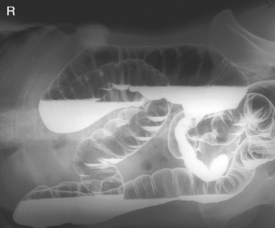

The air-barium distribution within the stomach and large intestine changes with various body positions. By knowing these distribution patterns, one can determine in which body position a radiograph was taken. Air always rises to the highest levels, and the heavy barium settles to the lowest levels (air is black, barium is white).

The ascending and descending portions are located more posteriorly, and thus more of these parts in general would be filled with barium (white) in the supine position and with air (black) in the prone position.

This much separation of barium and air occurs generally only with double-contrast barium-air studies.

Air-fluid levels would be seen in the erect position in which the air would rise to the highest position in each of the various sections of the large intestine, as shown in the accompanying figure.

Right and left decubitus projections (not shown on these drawings) also would demonstrate air-fluid levels, with air again rising to the highest portions.

Both right and left lateral decubitus are commonly taken as part of a double-contrast series.